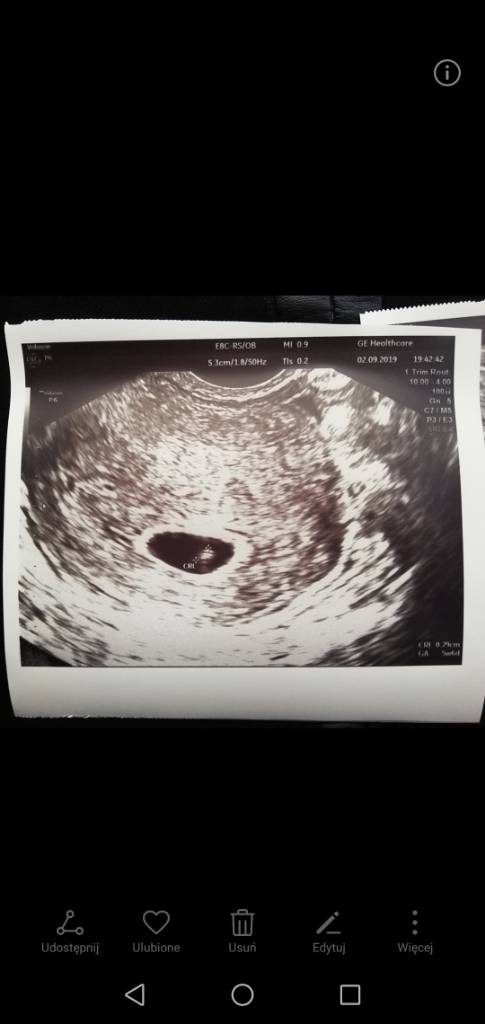

A ja byłam na szybko dziś u lekarza bo powiedziałam w pracy ze jestem w ciąży.. Bo chcieli mnie wysyłać na szkolenie jutro 80 km od domu a ja nie dam rady się tyle tluc autobusem. Wrzucam zdjęcie z 02.09 wtedy był wg Om 5t6d a dzisiaj wg om 10.09 7t1d

Widziałam jak serducho ładnie bije i mam zaświadczenie o ciąży następna wizyta na NFZ 24.09Zobacz załącznik 1020815Zobacz załącznik 1020816